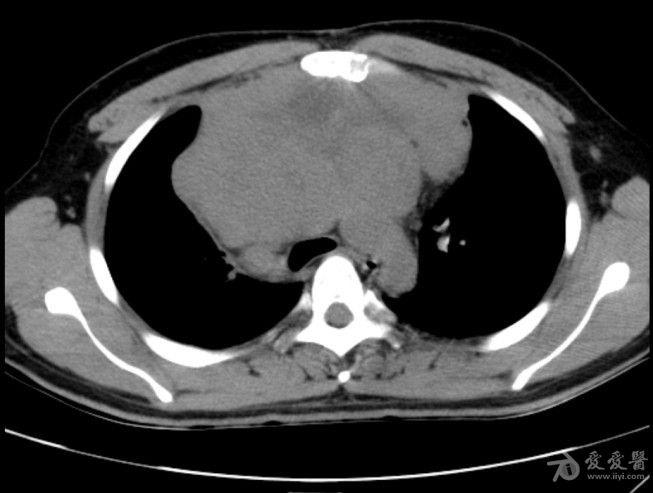

病例19恶性胸腺瘤

图片尺寸653x493

患者男,58岁,因"颜面水肿"于2011年9月至中山大学肿瘤防治中心就诊.